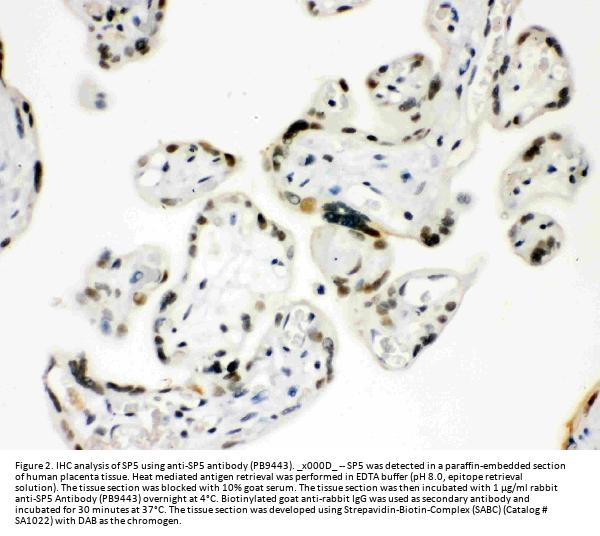

Immunohistochemistry (Paraffin-embedded Section), 0.5-1μg/ml, Human

Boster Bio Anti-Sp5 Antibody Picoband® catalog # PB9443. Tested in IHC, WB applications. This antibody reacts with Human. The brand Picoband indicates this is a premium antibody that guarantees superior quality, high affinity, and strong signals with minimal background in Western blot applications. Only our best-performing antibodies are designated as Picoband, ensuring unmatched performance.